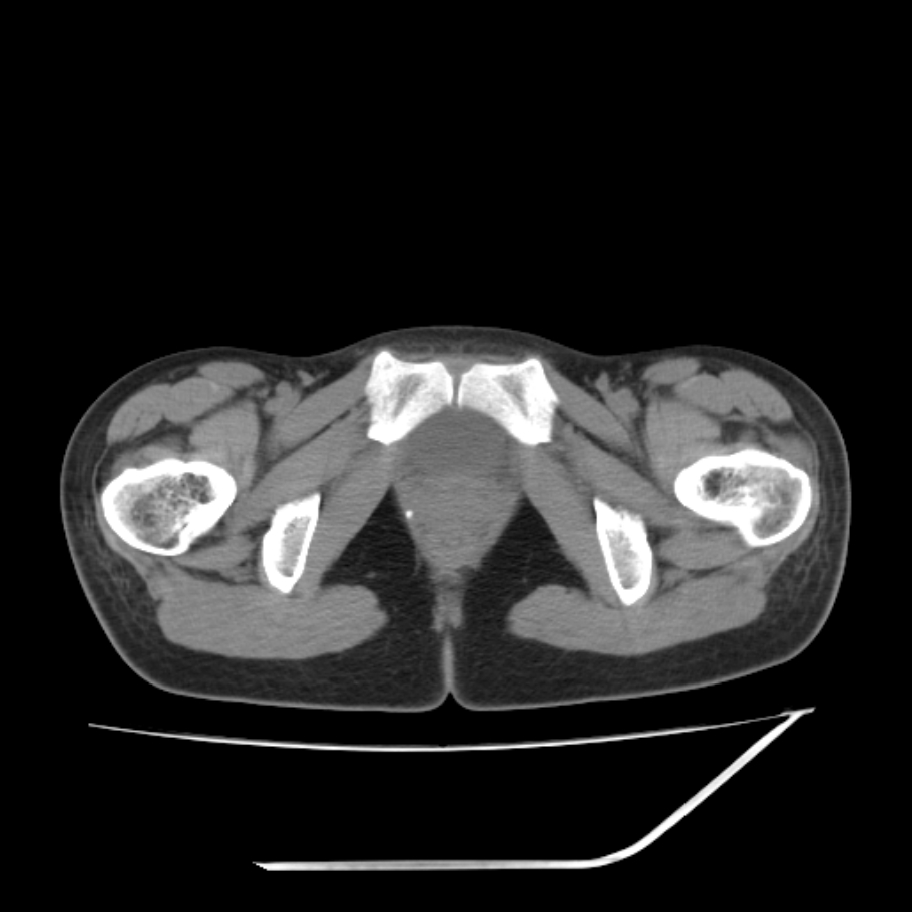

女,25岁。偶尔有右下腹不适感,余无明显异常。(结婚半年),囊壁较厚,是卵巢囊肿吗?

右侧卵巢区椭圆形囊性肿物,内壁光滑 无分隔。直肠子宫间隙内有少量积液征象。结合临床考虑卵巢巧克力囊肿,还要问问有没有痛经,本例ct怎么没有灌肠?要是灌肠或前一前口服造影剂,起码可以和肠管区别开

右侧囊性占位,1囊肿,2囊腺瘤。

b超示:囊实性占位,畸胎瘤?临床有痛经。

考虑右侧卵巢囊性占位性病变(巧克力囊肿?),盆腔积液有不排除宫外孕可能,请结合临床和b超。

右侧卵巢囊伴盆腔少量积液。